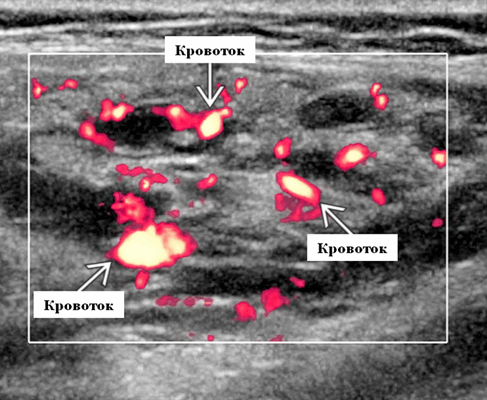

Лучший диагностический критерий. Неоднородно гипоэхогенное поражение, синусоидальные сосудистые пространства, движение вперед и назад в реальном времени ± эхогенные флеболиты. Выраженный сигнал потока на цветном или энергетическом доплеровском режиме. Монофазный низкоскоростной поток на импульсном доплеровском режиме

Результаты ультразвукового исследования. УЗИ в серошкальном режиме. Большинство сосудистых венозных гемангиом (80%) выглядят неоднородно гипоэхогенными. Большие анэхогенные сосудистые пространства видны менее чем в 50% случаев, серпигинозные и синусоидальные. Поражения с небольшими сосудистыми каналами могут казаться эхогенными (из-за множества акустических границ, отражающих звук). Определить пределы образования бывает трудно, так как компоненты поражения могут быть изоэхогенными в околоушной паренхиме и незаметно смешиваться. Внутрипросветное движение эхо-сигналов при УЗИ в реальном времени, представляющее медленный сосудистый кровоток. Характерны эхогенные флеболиты с задним акустическим затенением. Сообщается, что они присутствуют только в 20% ВСМ. Иногда поражается вся околоушная железа, имитируя диффузную или инфильтративную патологию. Целесообразность склеротерапии оценивается соотношением сосудистых пространств к эхогенной матрице

Импульсный допплер. Монофазный, низкоскоростной поток может иногда обнаруживаться в анэхогенных и гипоэхогенных пространствах, представляющих открытые сосуды со значительным кровотоком. Отсутствие допплеровского сигнала при медленном кровотоке или тромбировании

Цветной допплер. Выраженный цветной доплеровский сигнал присутствует в областях, где поток значительный. Используйте фильтр для стенок сосудов и низкую частоту повторения импульсов (PRF) для увеличения доплеровской чувствительности. Отсутствует допплеровский сигнал при медленном кровотоке или тромбировании. Доплеровский сигнал потока изменяется различными маневрами. В поверхностных участках доплеровский сигнал может быть остановлен прямым сжатием датчика над поражением. Сигнал потока может иногда быть усилен маневром Вальсальвы или дистальным сжатием, но последнее трудно выполнить в области лица.